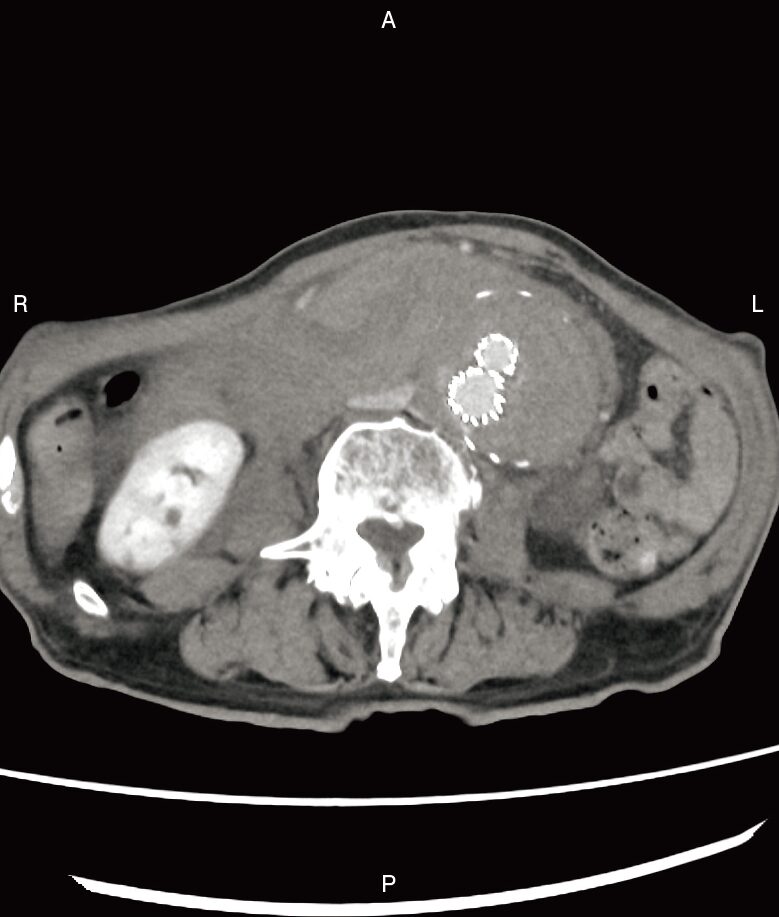

腹部造影CT像を示す。考えられるのはどれか。

まず、画像の中央(背骨のすぐ前)を見てください。 本来なら、500円玉くらいの大きさで丸く写るはずの「腹部大動脈」が、ソフトボールのように巨大に膨れ上がっています。これが「腹部大動脈瘤(AAA)」です。

※ちなみに、真ん中にある2つの極端に白いリング状の構造物は「ステントグラフト(人工血管)」です。この患者さんは過去に大動脈瘤の治療を受けていたものの、何らかの原因で再び圧力がかかり、限界を迎えてしまった状態だと推測できます。

✔ 大血管の周りに広がる「白いモヤモヤ」の正体

この画像の最も恐ろしい所見は、膨らんだ大動脈の周りに広がっている、ベチャッとした不整形の白いモヤモヤ(高吸収域)です。 脂肪や筋肉の隙間を埋め尽くすように広がっているこの影の正体は、血管から噴き出した「新鮮な血液(血腫)」です。 腹部大動脈は「後腹膜臓器」といって、お腹の背中側を走っています。 ここが破裂すると、血液は腹腔内(腸がある場所)ではなく、背中側の隙間(後腹膜腔)に一気に流れ込みます。これを「後腹膜血腫」と呼びます。

「大動脈が異常に太い」+「その周りに血液(高吸収域)が漏れ出ている」。 この2つの所見が揃えば、診断は 腹部大動脈瘤破裂で確定です。